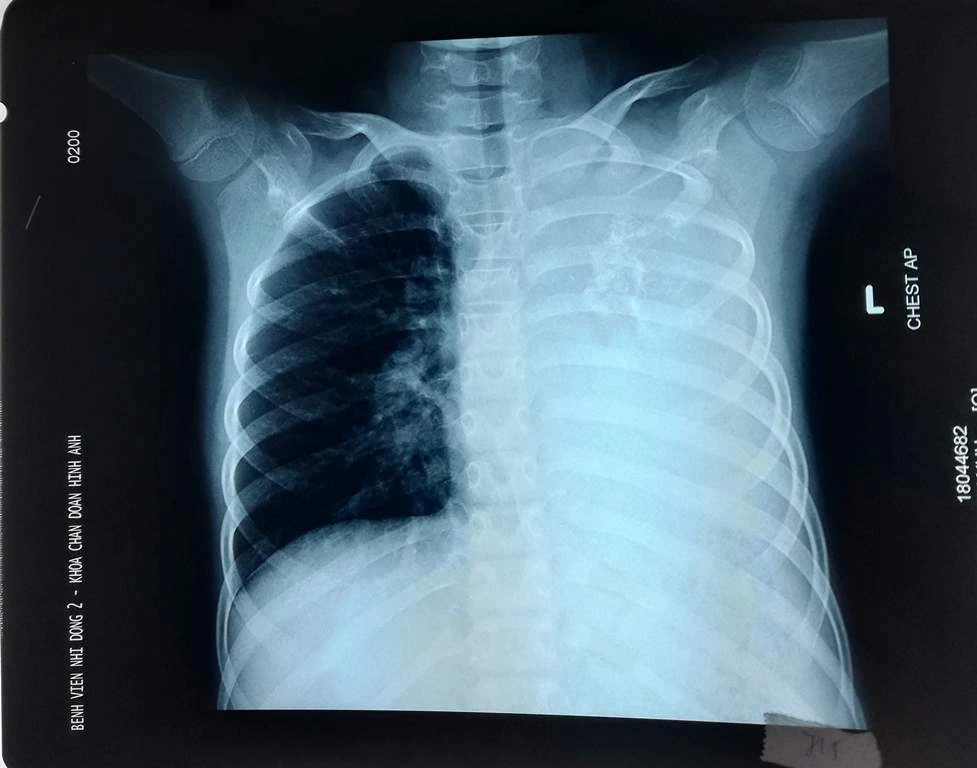

Bệnh nhi được người nhà đưa đến BV Nhi đồng 2 khám do ho kéo dài, khó thở khi gắng sức. Qua hình ảnh CT scan ngực, các bác sĩ phát hiện một khối u phổi khổng lồ xâm lấn toàn bộ phổi trái gây tắc đồng thời phế quản gốc trái và động mạch phổi trái, khiến bệnh nhi chỉ hô hấp bằng phổi bên phải.

Khối u khổng lồ xâm lấn toàn bộ phổi trái. Ảnh: BVCC